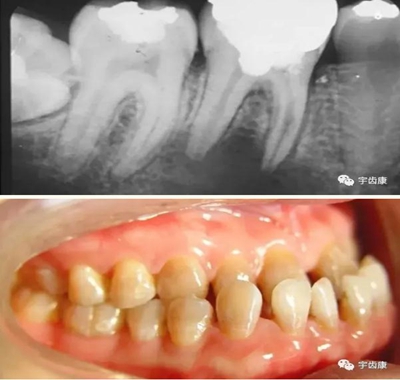

X線閱片知識